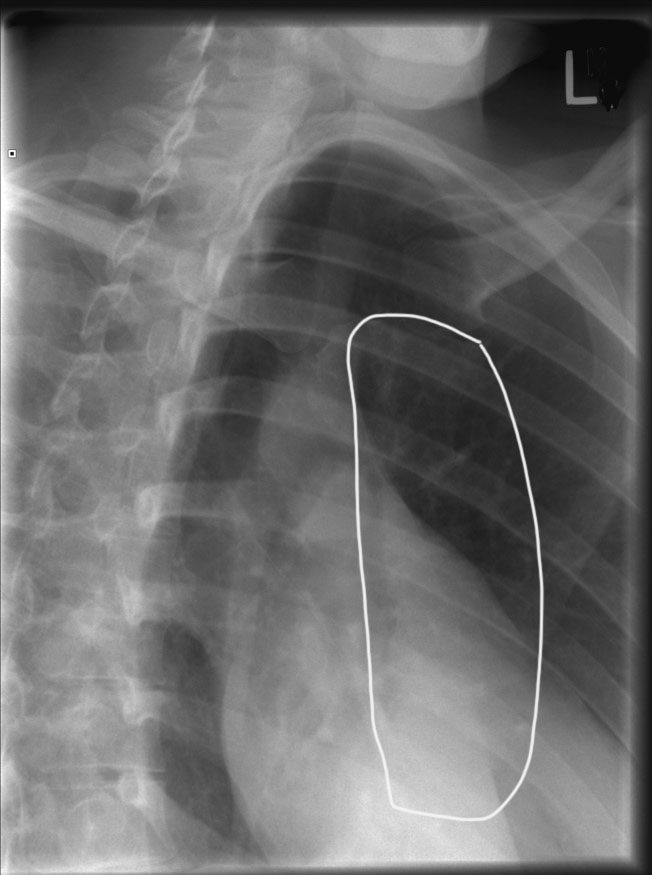

How is the patient positioned for a lateral sternum (erect)?

Arms and shoulders drawn back, chest out; mid-coronal plane perpendicular to IR.

Where is the CR for lateral sternum?

Perpendicular to mid-sternum, midway between jugular notch & xiphoid.

Why use increased SID (152–183 cm) for lateral sternum?

To reduce magnification caused by large OID.

What indicates correct positioning in lateral sternum?

Sternum free of rib/shoulder overlap, sharp bony detail, superimposed anterior ribs.